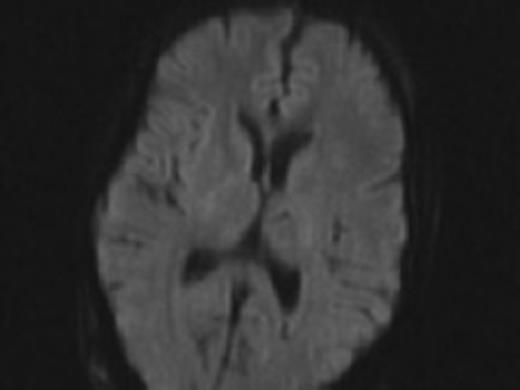

Difussion MRI of the brain prior to syndrome showing no areas of stroke.

Thereafter, her ventricles diminished in size back to their baselines and her neurological exam slowly improved back to her baseline over the course of 2 months. She had no lesions noted in the opercular regions on her MRI post operatively (Fig. 4).